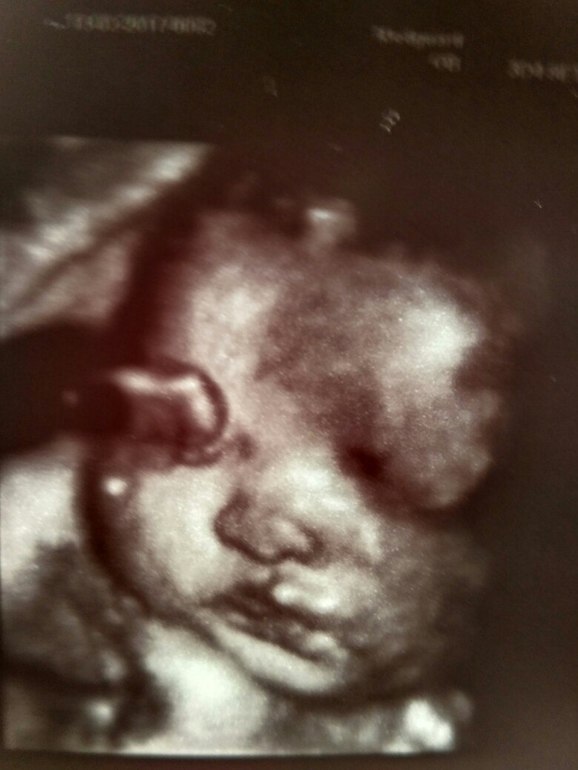

Мои предположения о достаточно крупном малыше развеялись. 1960 гр. на сегодняшний день. Прогноз к родам - что-то около 3 кг (как и Уля - 3080). С длинноногостью, похоже, тоже облом - все соответствует сроку беременности. Мужнина надежда на 2% рухнула. Врач так и сказал: "Пирожок между ножками". А еще: "Ну и щеки же она у вас наела" - говорит. И правда))

У Ульки скромнее были) Они, кстати, похожи друг на друга, девчонки мои. Ну все, папа, покупай вторую винтовку - женихов отгонять))